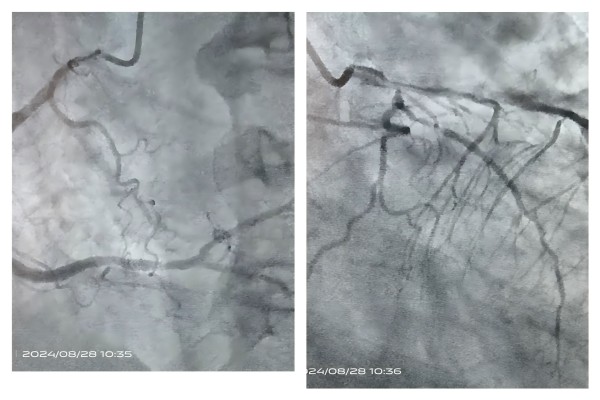

7 时 38 分,救护车历经 20 多公里盘山路抵达患者家中。7 时 40 分,王文娟医生再次行床旁心电图,向家属告知病情,排除溶栓禁忌后,详细阐述即刻溶栓的重要性和必要性,取得家属同意。张江花护士立即为患者静脉采血,7 时 50 分建立两组静脉通路;7 时 54 分,静脉推注肝素钠 3600u;8 时 01 分,静推第一支溶栓药瑞替普酶 18mg。8 时 18 分,患者胸闷、气短症状减轻,经仔细观察皮肤黏膜无出血点后,将患者抬上救护车,给予吸氧、心电监护、血氧饱和度监测等,迅速赶往医院。8 时 34 分,在救护车上静推第二支溶栓药瑞替普酶 18mg。8 时 39 分,救护车绕行急诊科,将患者安全送至心内科 CCU 病房。10 时 10 分,患者胸闷、气短症状消失,急诊行冠脉造影术,提示冠脉三支病变,前降支血流 3 级,溶栓再通。

(溶栓后血管造影)